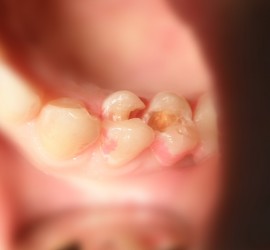

Аномалии строения и пороки развития зубов Пороки тканей зуба многообразны, они могут проявляться изолированно и сочетаться с аномалиями строения и пороками развития органов и систем всего детского организма, в том числе челюстно-лицевой области. Ткани зуба имеют эктодермальное (эмаль) и мезодермальное (дентин, пульпа, цемент) происхождение. В связи с этим пороки эмали […]